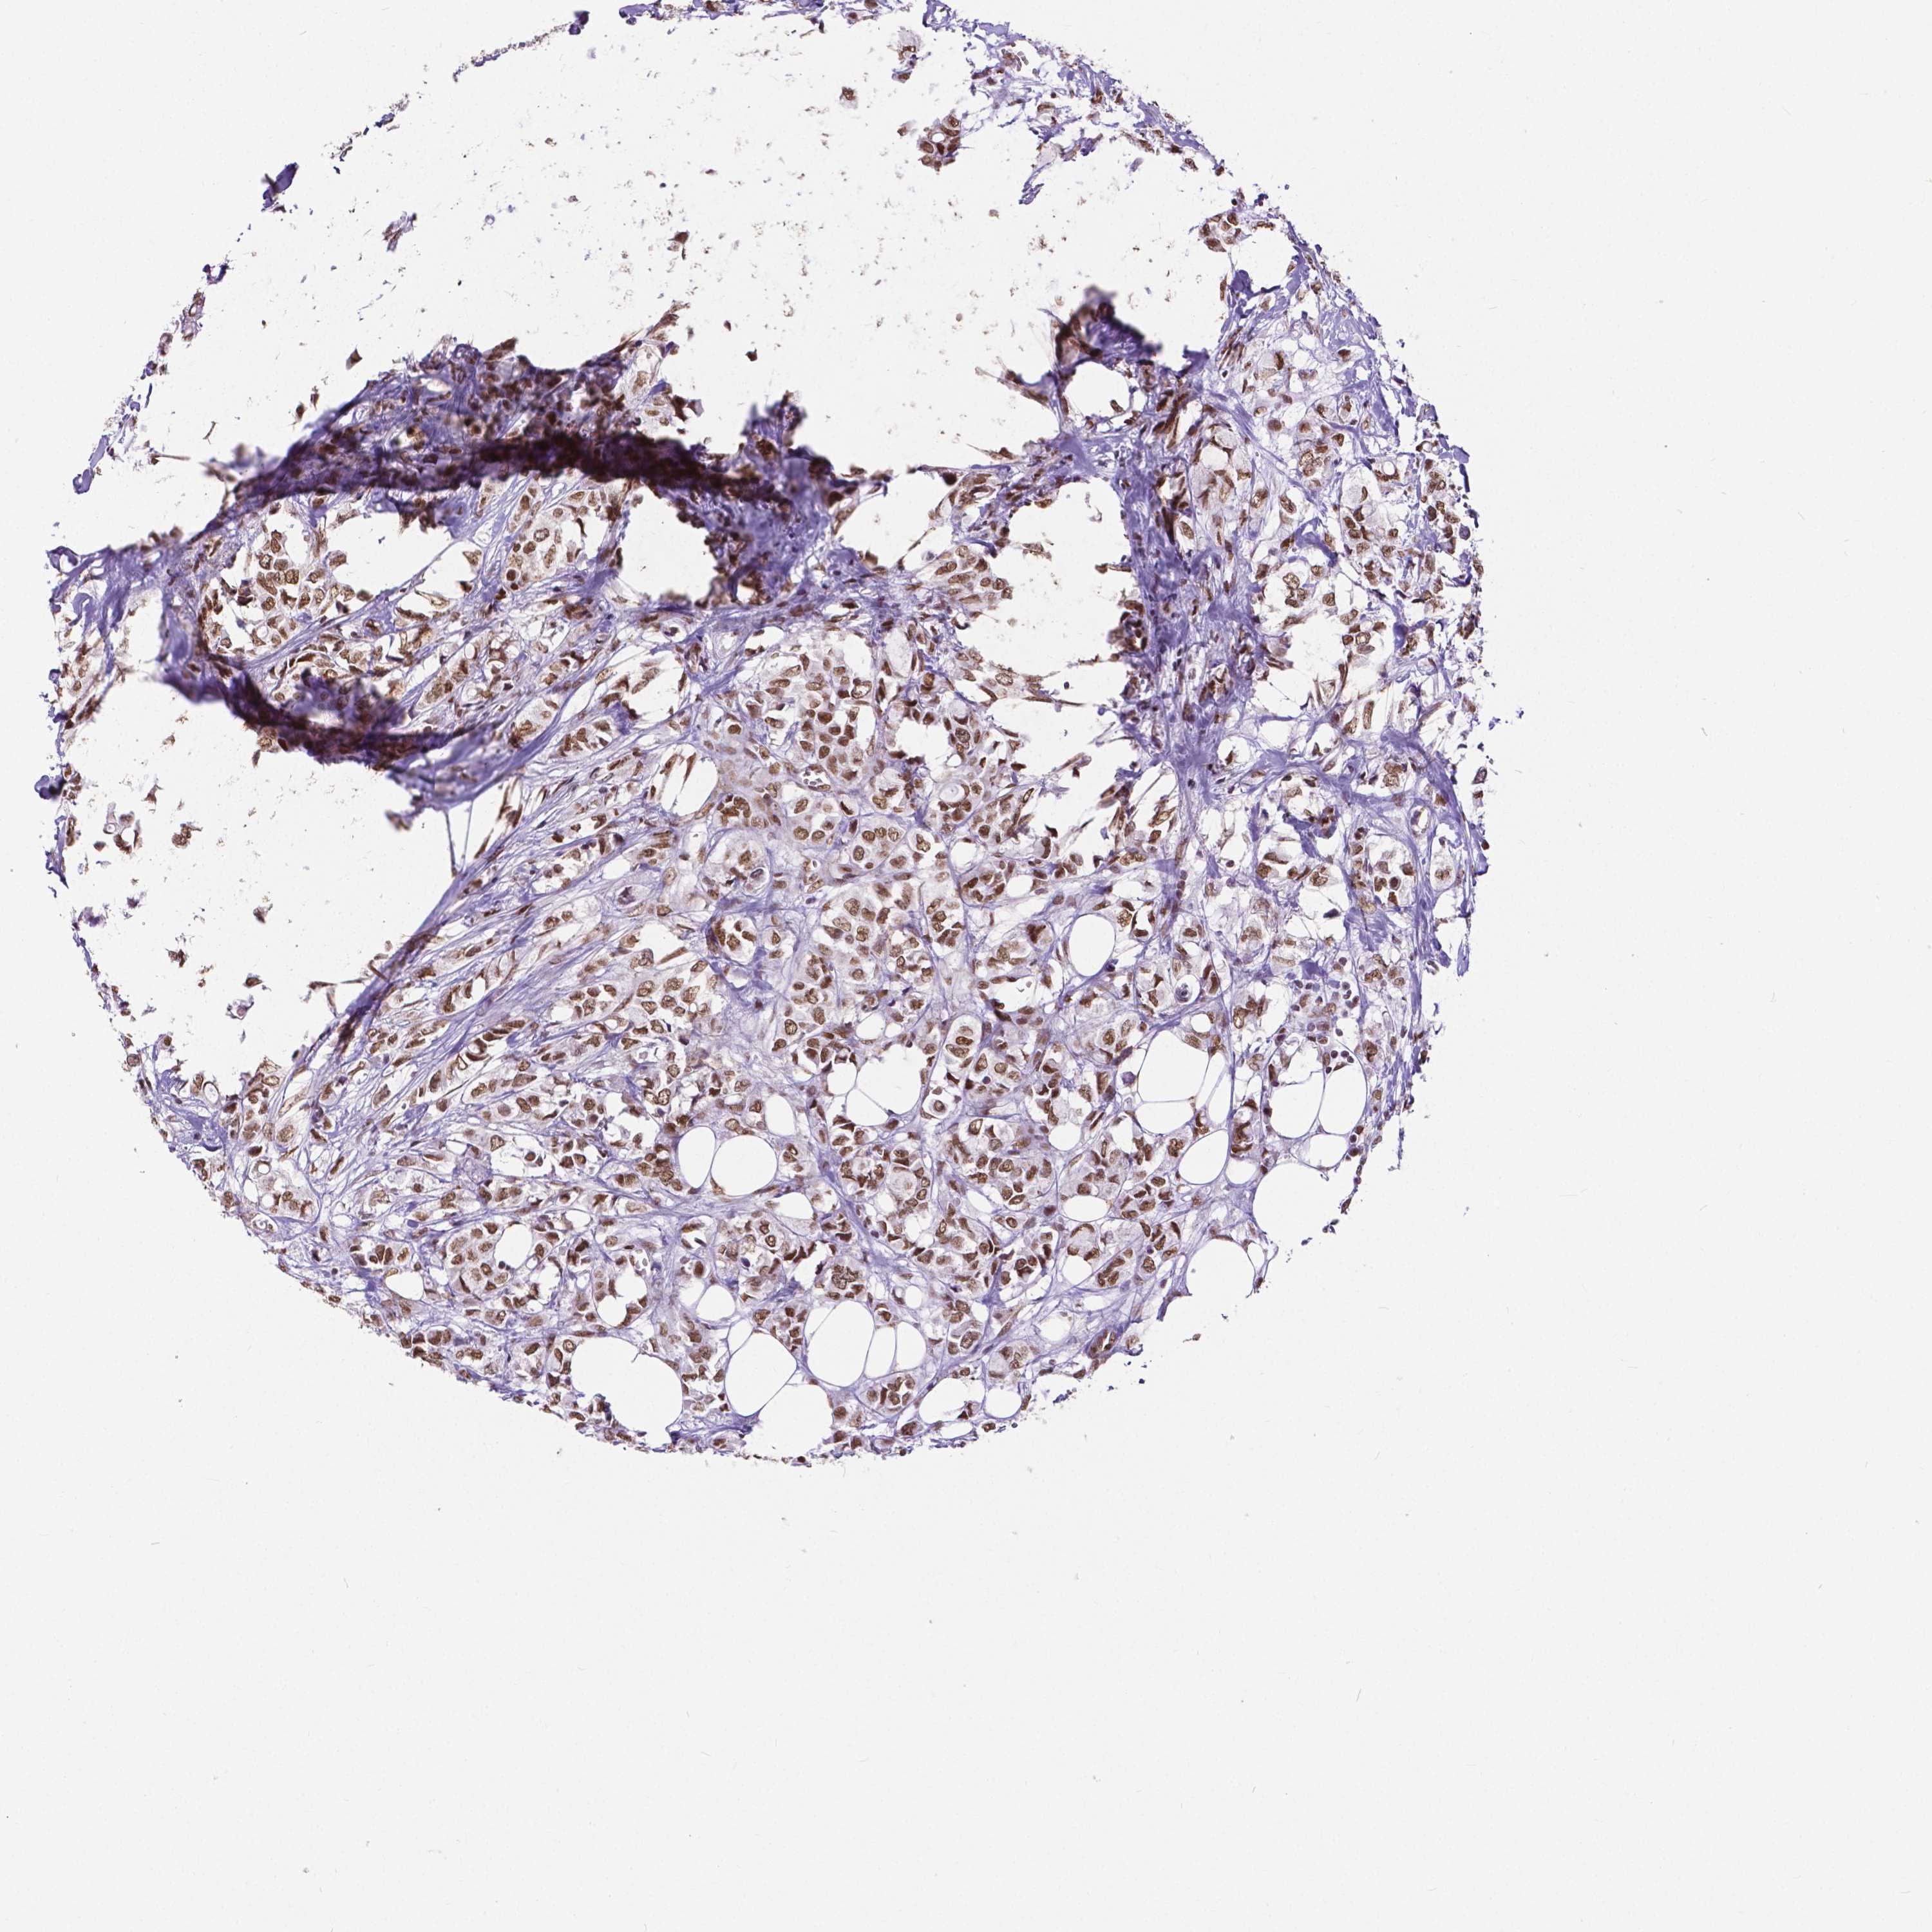

CANCER BREAST CANCER Show tissue menu

BRCA TCGA BRCA VALIDATION PROTEIN EXPRESSION

ANTIBODIES

AND

VALIDATION